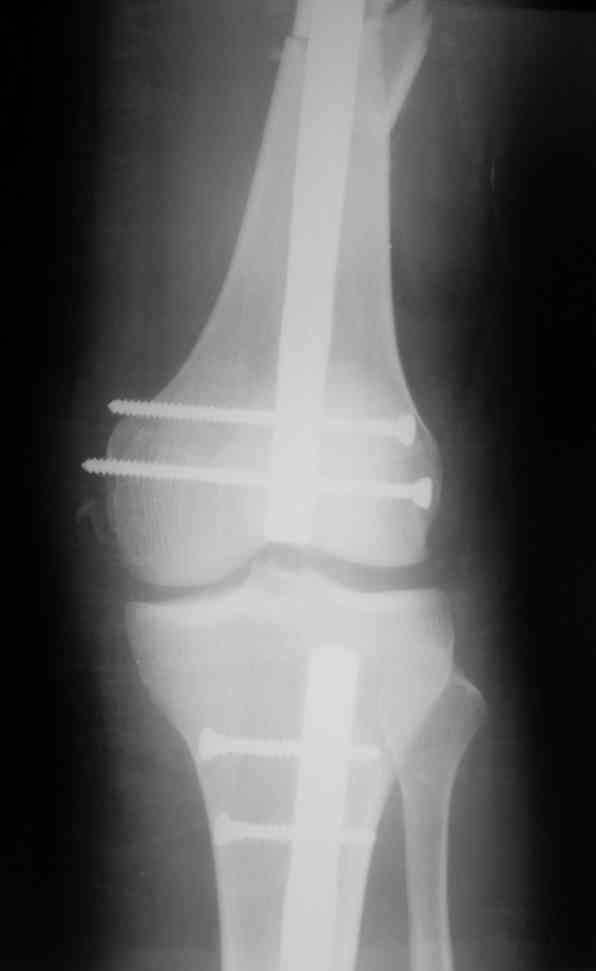

Дорогой Александр. Имею скромный опыт использования системы Fixion при переломах плеча, бедра и тибии. Всего 18 наблюдений с сентября 2006 г. Результаты отличные. Гвоздь индивидуален для каждого медуллярного канала. Легко имплантируется как в узкий, так и в деформированный канал. Это позволяет применять метод интрамедулярного остеосинтеза без ненужных потерь времени операции, флюороскопии и реально снижает крвопотерю и операционный риск. Удаление происходит без проблем. Особенно интересны больные с ипсилатеральными переломами бедра и голени.

> Особенно интересны больные с ипсилатеральными переломами бедра и голени.

Да, спасибо за интересные иллюстрации. Получилось очень симпатично. На большеберцовой кости непременно надо было винты? Там же был торцовый упор, перелом в средней трети?